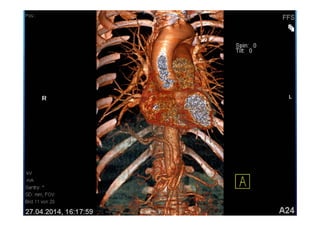

52 jährige Patientin

Gewichtsverlust

Adynamie

Nachtschweiß

Immer wieder Fieber über 12 Monate

Raucherin > 30 packyears

Lungensequester mit

infradiaphragmaler arterieller

Blutversorgung